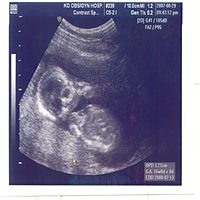

懷孕已經8個多月了,寶寶也都很健康的在長大

因為是女寶寶的關係,想要她的皮膚看起來很好

白白嫩嫩的,除了多吃水果、喝豆漿之外,